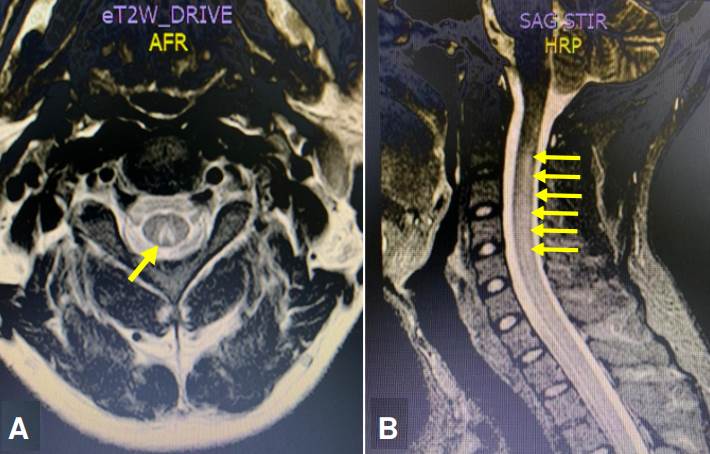

La paciente aportó una electromiografía con conducción nerviosa que reportaba una radiculopatía de la vertebra lumbar L5. Se practicó una resonancia magnética (RM) con gadolinio, de columna cervical y dorsal. Se observó una hiperintensidad que comprometía los cordones posteriores de la médula espinal cervical y dorsal, sin captación del medio de contraste (figura 1). Se sugirió una mielopatía por déficit metabólico de vitamina B12, ácido fólico o cobre, o un proceso inflamatorio de tipo infeccioso por virus linfotrópico humano de células T de tipo I o II (HTLV-I/II).

Típicamente no existe captación del medio de contraste, sin embargo, posterior a su administración, se podría ver el realce de la región posterior y lateral de la médula espinal en la secuencia T1 21. Estos hallazgos imagenológicos y clínicos son indistinguibles a los que se presentan en la mielopatía por déficit de cobre 20. De igual forma, hay que resaltar que en la secuencia STIR (Short Time Inversión Recovery) se observa usualmente una hiperintensidad en la mayoría de las mielopatías 21, como en las imágenes de RM presentadas en los casos 1 y 2.